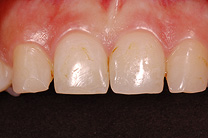

Ist ein Zahn sehr stark oder bis unter das Zahnfleisch zerstört, kann er nicht mehr mit einer herkömmlichen Kunststofffüllung versorgt werden. Der noch vorhandene Restzahn lässt sich nur noch durch eine Krone restaurieren. Sie besteht aus einem individuell gegossenen Metallgerüst, auf welches in mehreren Schichten Keramik aufgebrannt wird oder kann als rein vollkeramische Krone hergestellt werden, was zu einer noch höheren Ästhetik führt.

Die Restauration eines Zahnes mit einer Krone ist aufwendig. In einem ersten Schritt wird Karies und das alte Füllungsmaterial vollständig entfernt und der Zahnstumpf wieder aufgebaut. Eine präzise Abformung der Situation dient dem Zahntechniker als Grundlage für ein Gipsmodell, auf dem er die Krone herstellt. Sofern Farbe und Form perfekt stimmen, kann die Krone in einer zweiten oder dritten Sitzung beim Zahnarzt zementiert werden. Für die Zeit zwischen Präparation des Zahnes und dem definitiven Zementieren der Krone wird der Zahn mit einem individuell hergestellten Provisorium versorgt.